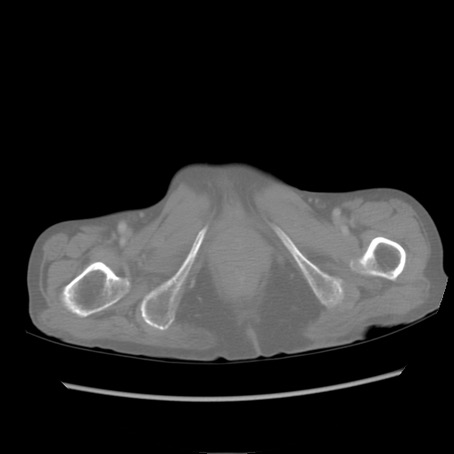

症例25(横断像)

【症例】80歳代女性

【主訴】胸のつかえ感

【現病歴】約9時間前に食後から胸のつかえた感じあり、嘔吐あり、来院。

【既往歴】胃癌(全摘)、胆摘、虫垂炎

【身体所見】心窩部に圧痛あり、反跳痛なし。

【データ】WBC 5700、CRP 0.05